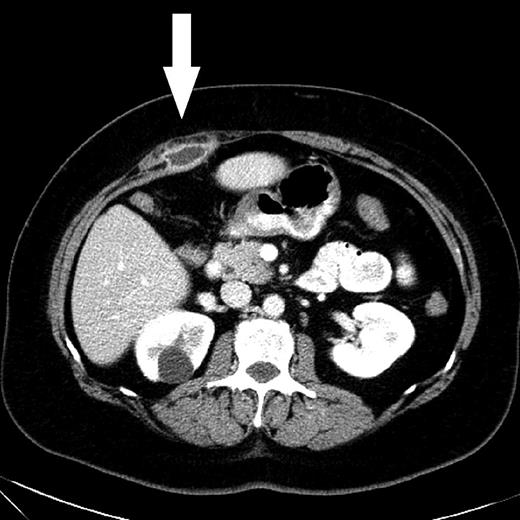

A computed tomography (CT) scan showed a 2.7 cm wide abscess in the Douglas pouch (Fig. 1). Anoscopy showed no rectal communication or other anorectal pathology and the abscess was drained transvaginally. Microbiological testing was positive for Enterococcus faecalis.

CT scan shows an abscess with peripheral rim enhancement in the Douglas pouch.